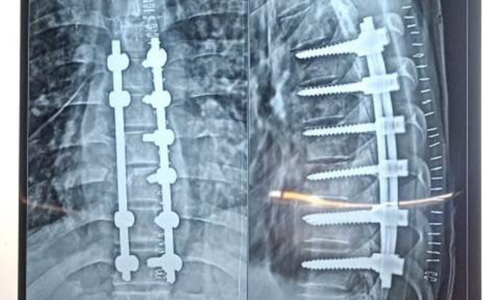

Cervical Myelopathy

Cervical Myelopathy Expert Care by Dr. Nitish Agrawal – Best Spine Surgeon in Pune Cervical Myelopathy is a serious spinal condition in which the spinal cord in the neck (cervical spine) becomes compressed. This compression is most commonly caused by degenerative changes in the spine, such as cervical disc prolapse,…